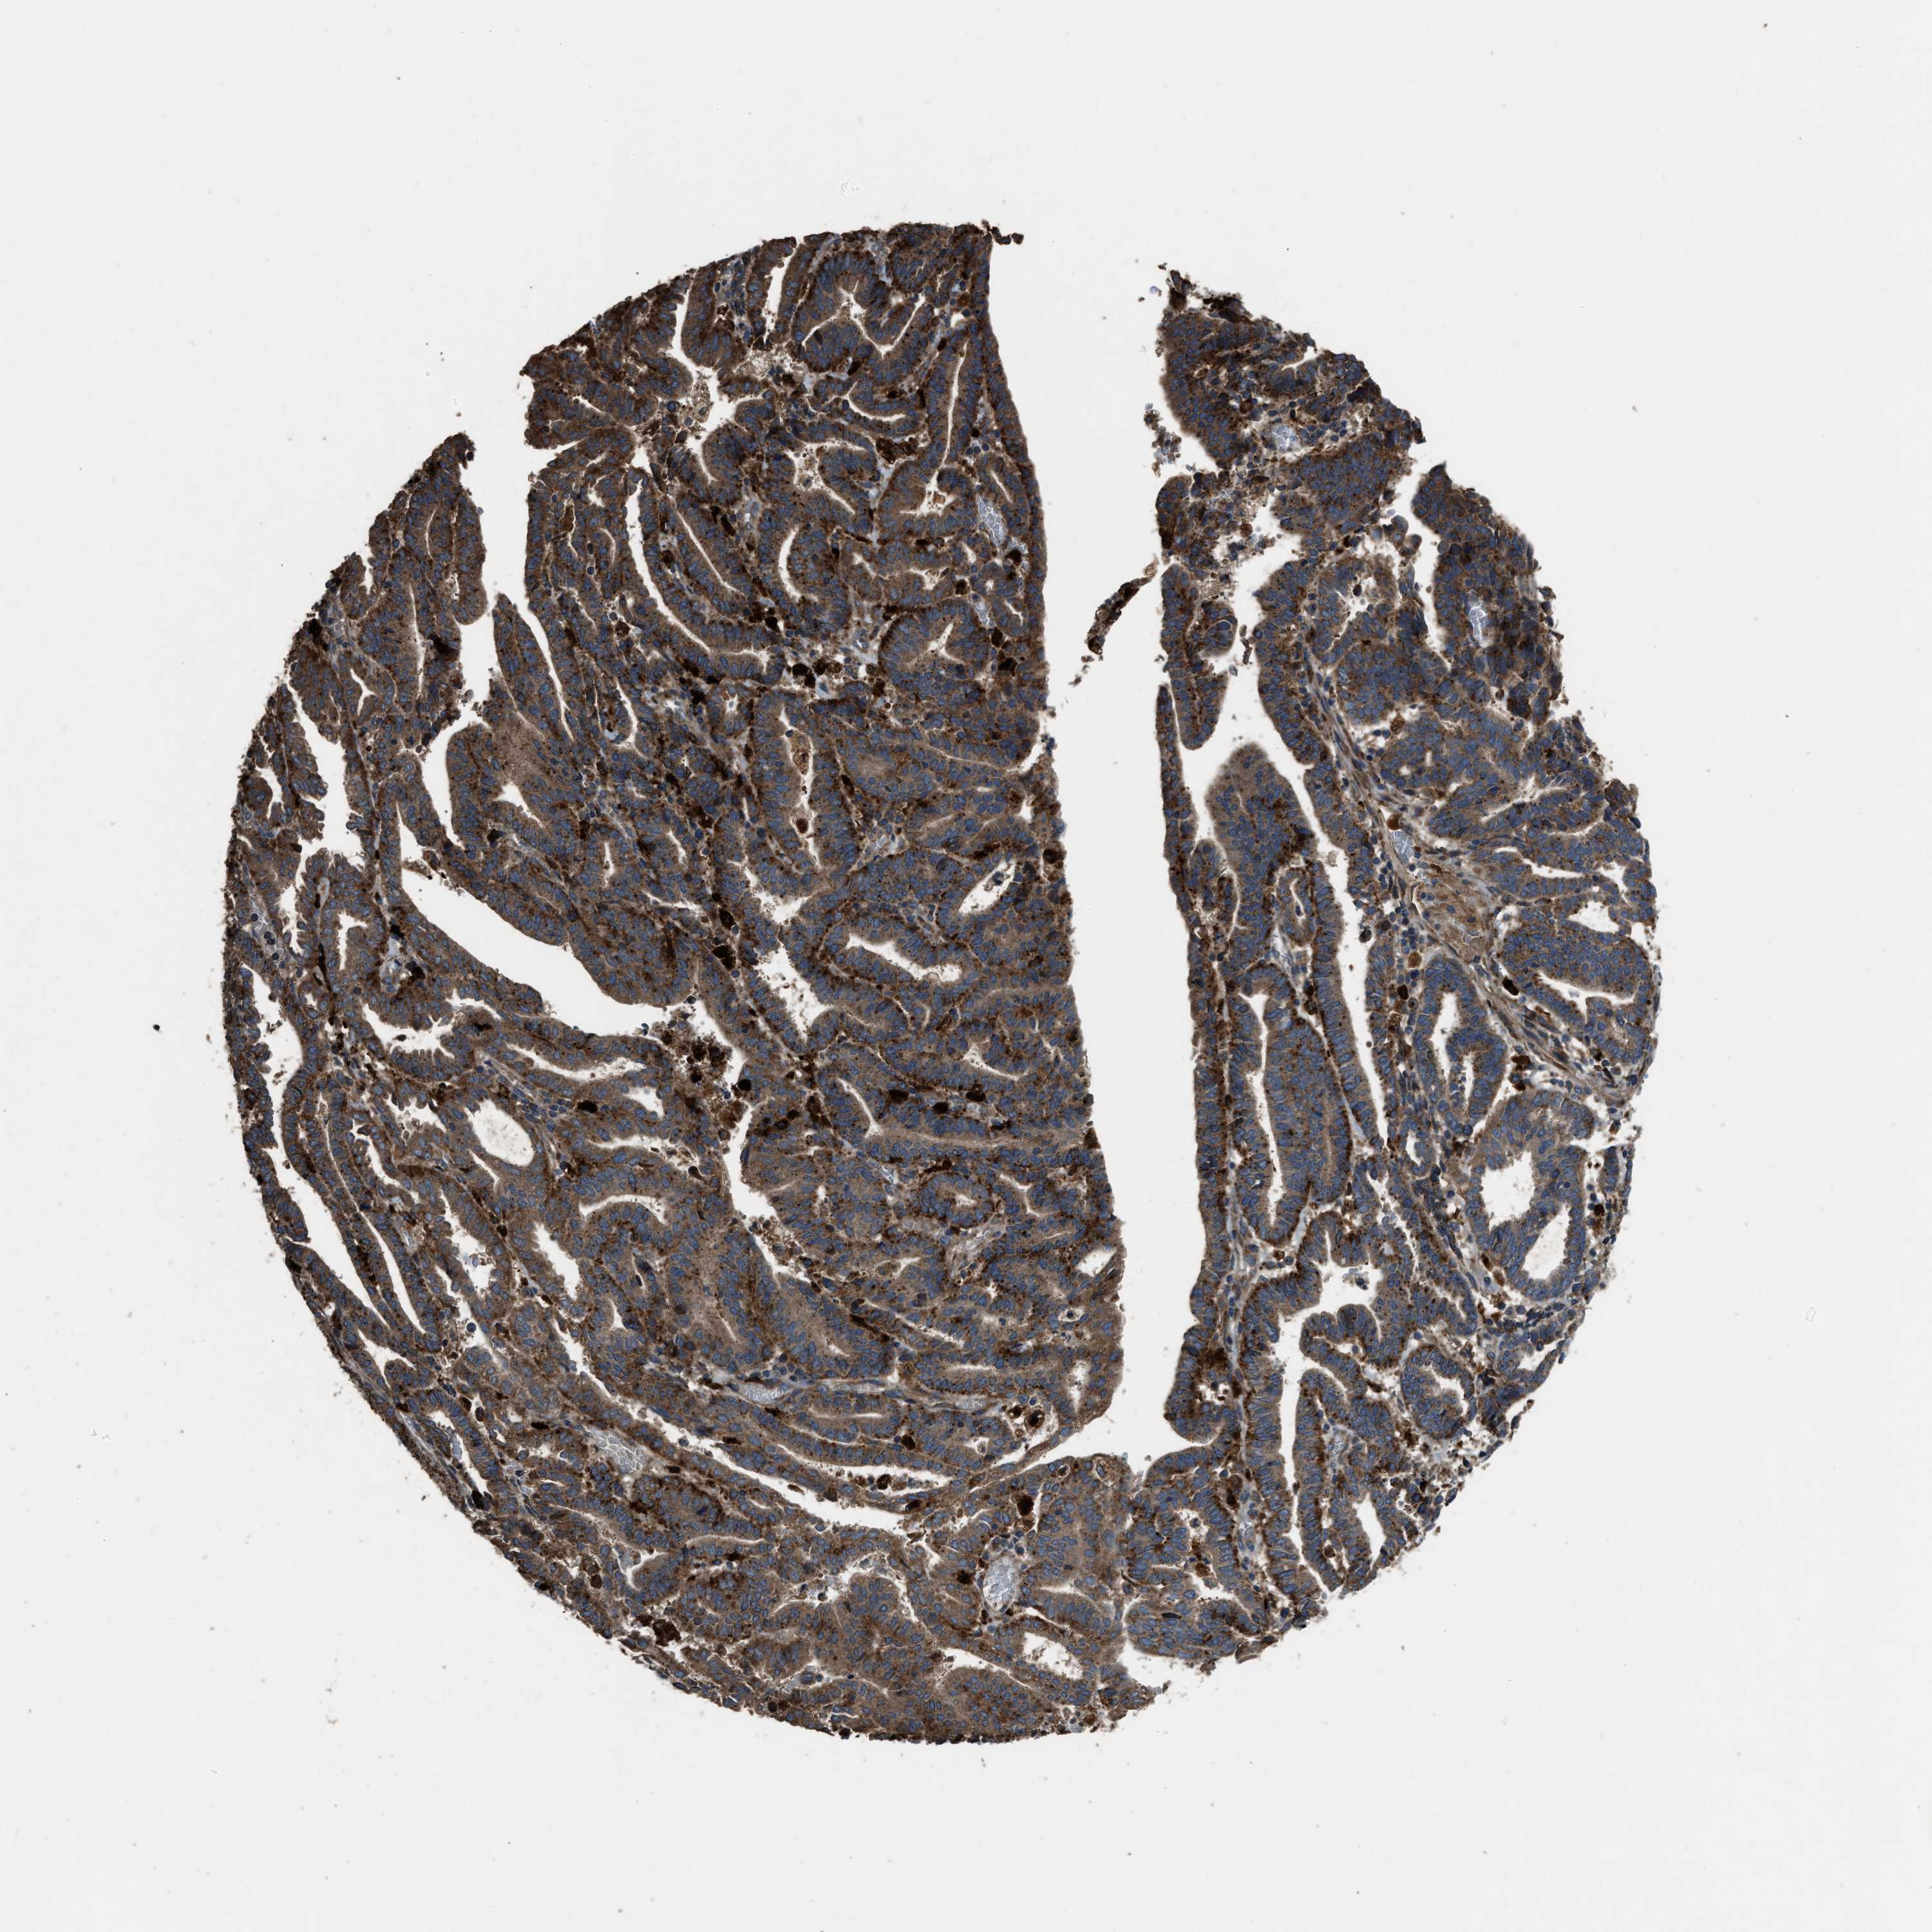

ENDOMETRIAL CANCER - Protein expressioni

A mouse-over function shows sample information and annotation data. Click on an image to view it in a full screen mode. Samples can be filtered based on level of antibody staining by selecting one or several of the following categories: high, medium, low and not detected. The assay and annotation is described here.

Note that samples used for immunohistochemistry by the Human Protein Atlas do not correspond to samples in the TCGA dataset.

Antibody stainingi

Antibody staining in the annotated cell types in the current human tissue is reported as not detected, low, medium, or high, based on conventional immunohistochemistry profiling in selected tissues. This score is based on the combination of the staining intensity and fraction of stained cells.

Each image is clickable and will lead to virtual microscopy that enables deeper exploration of all samples and also displays staining intensity scores, fraction scores and subcellular localization as well as patient and tissue information for each sample.

Antibody HPA025226

Antibody CAB019296

Staining

High

Medium

Low

Not detected

Intensity

Strong

Moderate

Weak

Negative

Quantity

>75%

75%-25%

<25%

None

Location

Nuclear

Cytoplasmic/membranous

Cytoplasmic/membranous,nuclear

Adenocarcinoma, NOS

Adenocarcinoma, metastatic, NOS